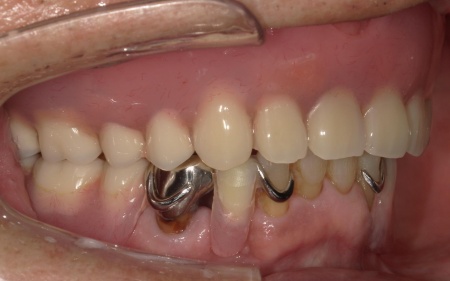

傷が治り、インプラントが顎の骨にしっかりと結合したことを確認したら、インプラントの頭部分に入れ歯と連結するための部分となる「アタッチメント」を装着しました。

次に、上顎には「インプラント支持型義歯(インプラントオーバーデンチャー)」を金属床義歯で作製します。

最後に、完成した入れ歯を装着し、噛み合わせや使用感に問題がないことを確認して、治療を終了しています。